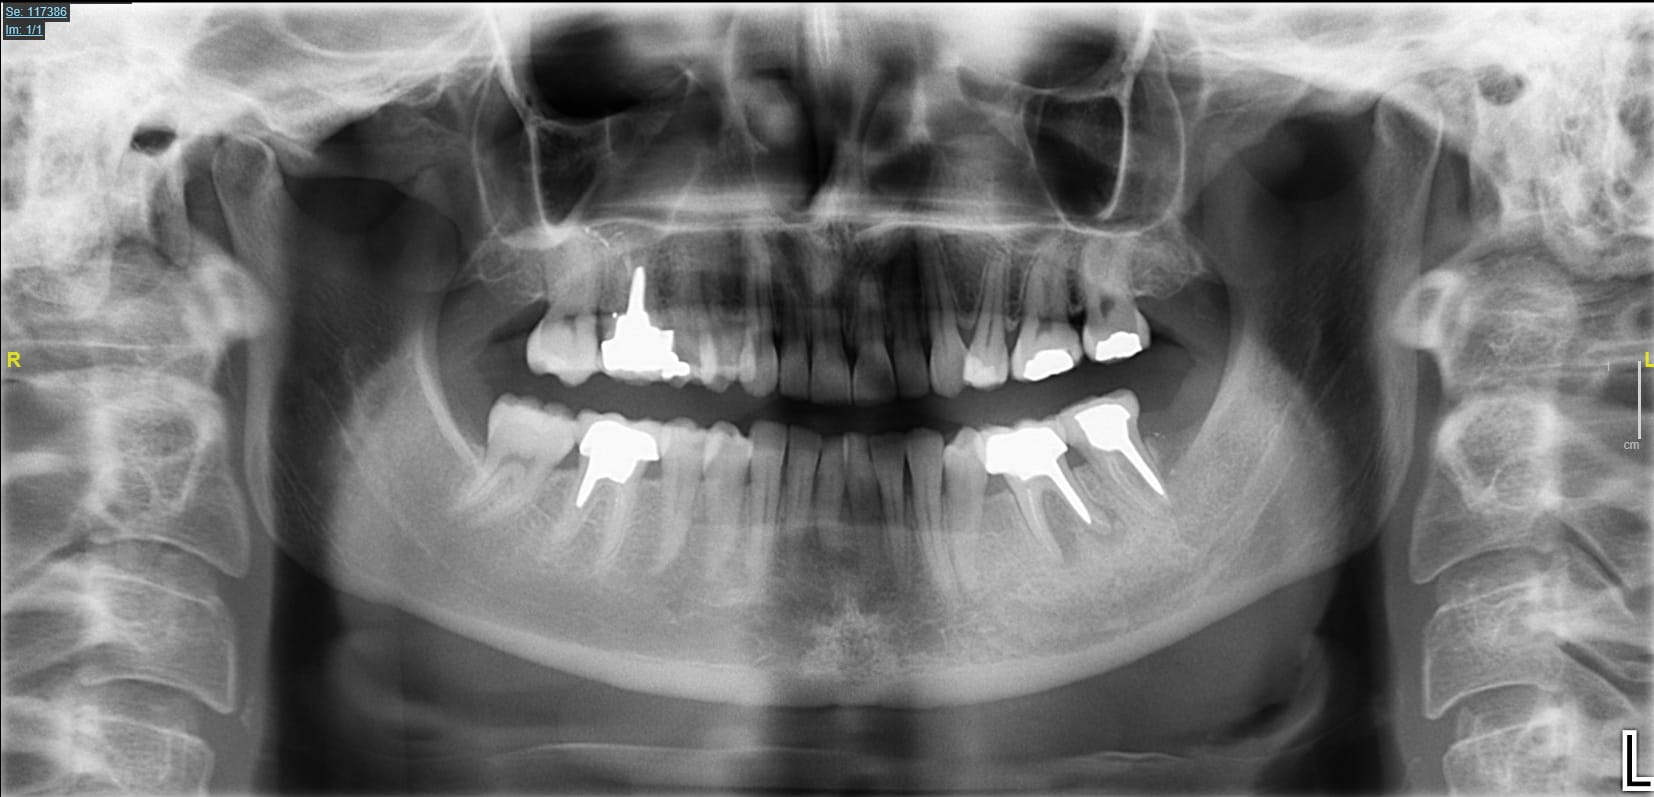

Ici une 37, complètement asymptomatique après un "soin" remontant à 5 ans...

Image extraite d'une pano.